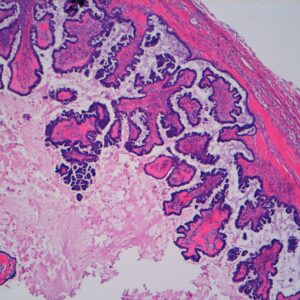

50-year-old female with visible hematuria